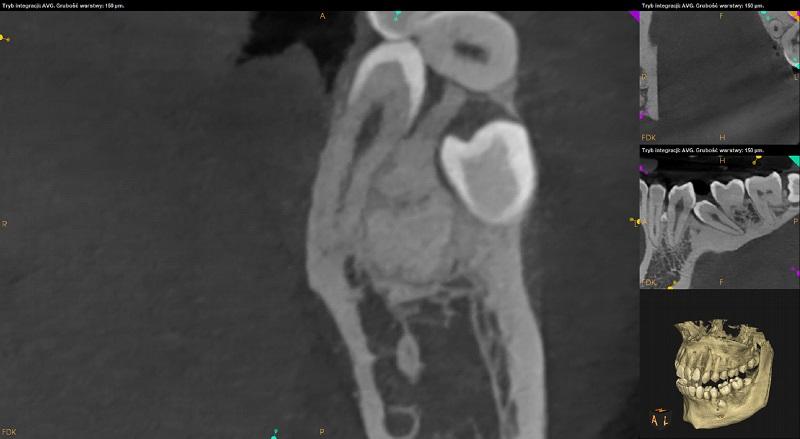

Ząb 38 – częściowo zatrzymany. Położony poziomo, koroną skierowany w stronę mezialną. Wierzchołki korzeni zagięte. Kanał nerwu zębodołowego dolnego biegnie po stronie językowej potem poniżej zęba 38. Korzenie w kontakcie z kanałem. Poziom wyrostka po stronie dystalnej zęba 37 obniżony.